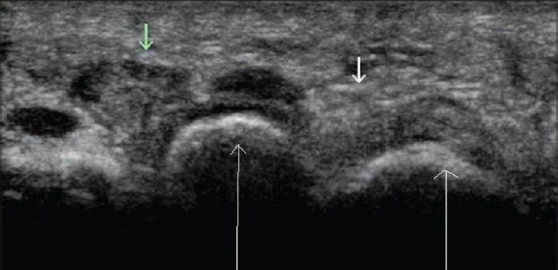

- 🔹 Prueba de elección. Debe realizarse con transductores lineales de alta frecuencia (10-18 MHz).

- 🔹 Hallazgo característico: masa hipoecoica, bien delimitada, de forma ovalada o redondeada, localizada en el espacio interdigital, entre las cabezas metatarsianas, justo por debajo del ligamento metatarsiano transverso.

- 🔹 Tamaño: suele medir entre 5 y 10 mm de diámetro. Puede haber un pequeño derrame en la bursa intermetatarsiana adyacente.

- 🔹 Doppler: generalmente ausencia de flujo vascular (a diferencia de las bursitis inflamatorias).

- 🔹 Dinámica: la maniobra de Mulder bajo visión ecográfica puede mostrar el desplazamiento del neuroma y confirmar el diagnóstico.

Hallazgo ecográfico característico